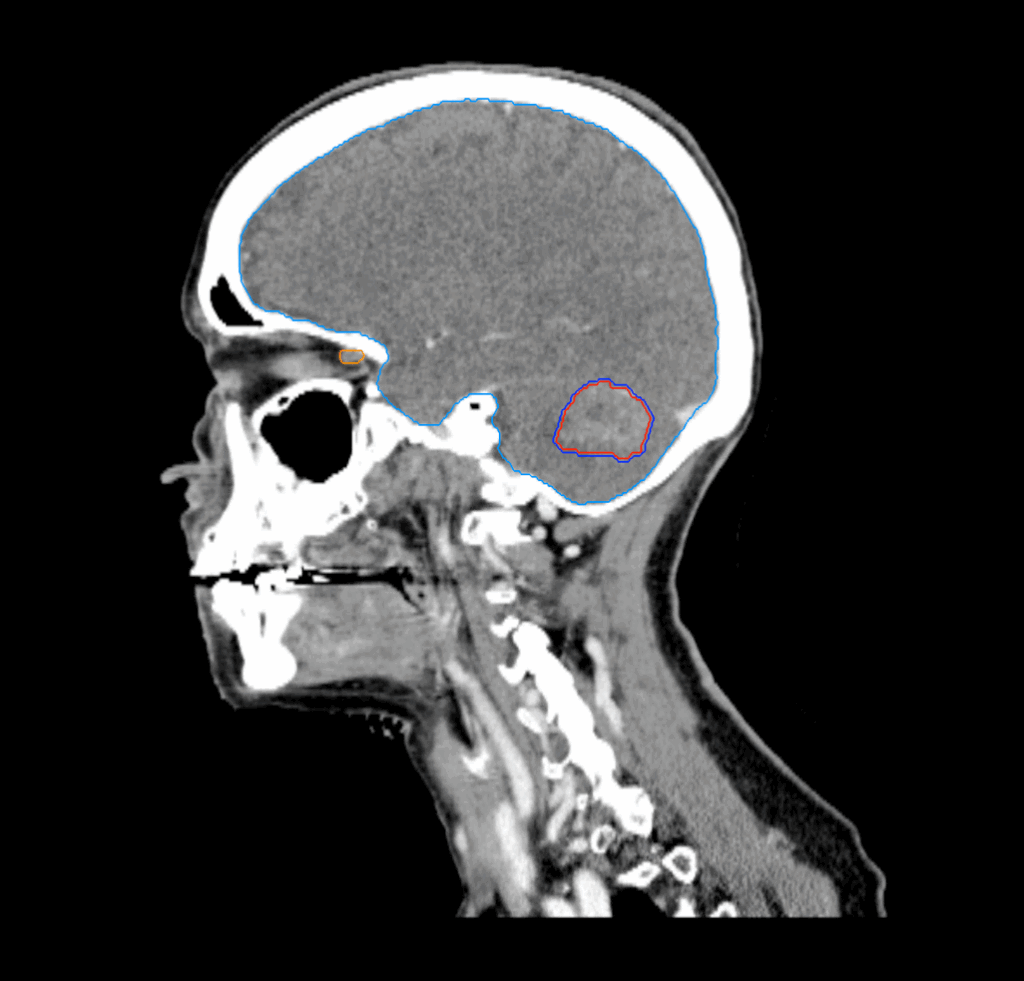

Planning CT Images

MRI: metastasis in the cerebellum, measuring 3.2cm